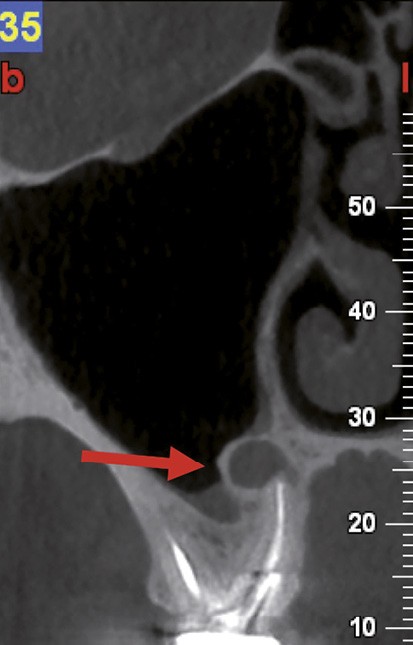

Si les isthmes sont particulièrement mis en évidence au niveau des molaires mandibulaires, cela devient médicalement important au niveau des molaires maxillaires.

La diffusion bactérienne et de leurs toxines, au niveau des molaires maxillaires est à l’origine d’un grand nombre de sinusites maxillaires chroniques, d’origine dentaire. Celles-ci sont principalement causées par l’absence de traitement du deuxième canal MV, qui existe dans 90 % des cas, et il est à noter que ces deux canaux – MV1 et MV2 – sont également reliés par un isthme.

Le nettoyage des isthmes intercanalaires reste un réel problème, et semble responsable de nombreux échecs [43]. Par ailleurs, il est nécessaire d’utiliser des instruments qui évitent de propulser les débris, tant apicalement que latéralement, en obturant les entrées isthmiques avec des débris compactés.